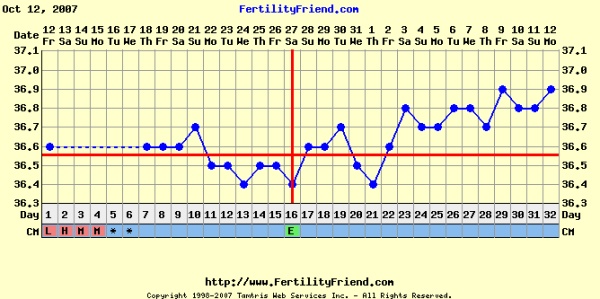

Krisz, nagyon jól alakul a görbéd